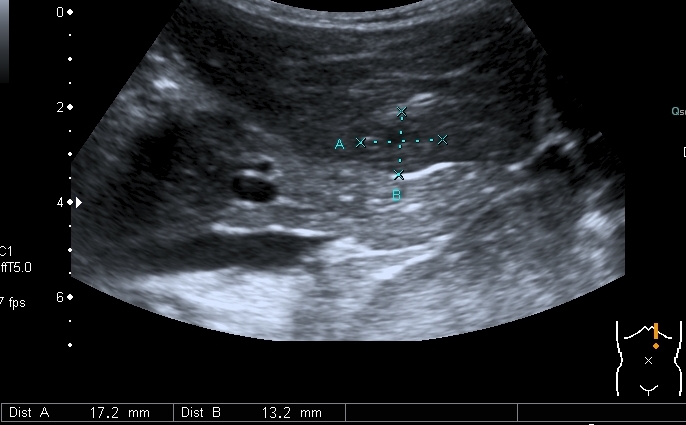

Добавляю сканы печени, я думаю они являются хорошей подсказкой о природе изменений в лёгких

Добавляю источник изменений в легких, печени и забрюшинном пространстве

По сложившейся тактике при обнаружении опухолевых образований мы не занимаемся морфологической верификацией, а отправляем ребёнка в головное учреждение, наверное это правильно - в лечении детских опухолей иногда бывают важны даже часы. Тем не менее , по УЗИ картине больше данных за нефробластому - есть остатки деформированной собирательной системы в области нижнего полюся образования, там же - немного ткани, похожей на нормальную почечную.

ЦДК образований в лёгких не делал, если быть откровенным, порядок находок у этого пациента был следующим: МТС в печени - изменения в нижней доле правого лёгкого - забрюшиное пространство - левая почка - левое лёгкое - правое лёгкое - рентген лёгких. Картина в комплексе была и так ясна, т.е. то, что это MTS сомнений не вызывало. Ну а после патогномоничной рентгеновской картины - вопросов тем более не было.